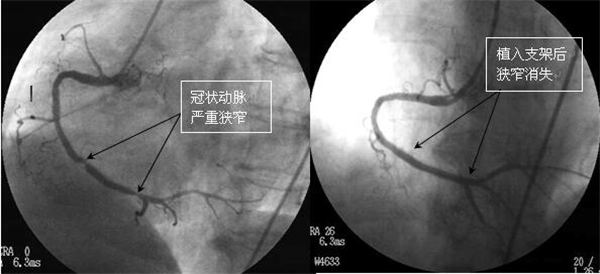

入院后,在心内科张丽琨主任的主持下,为刘师傅在局部麻醉的情况下进行了冠状动脉加支架植入手术。穿刺外周血管建立通路,在X光透视监视下将导管送达冠状动脉开口处,用特殊的传送系统将支架输送到病变部位,加压释放支架后撤出导管,不到一小时手术顺利结束。